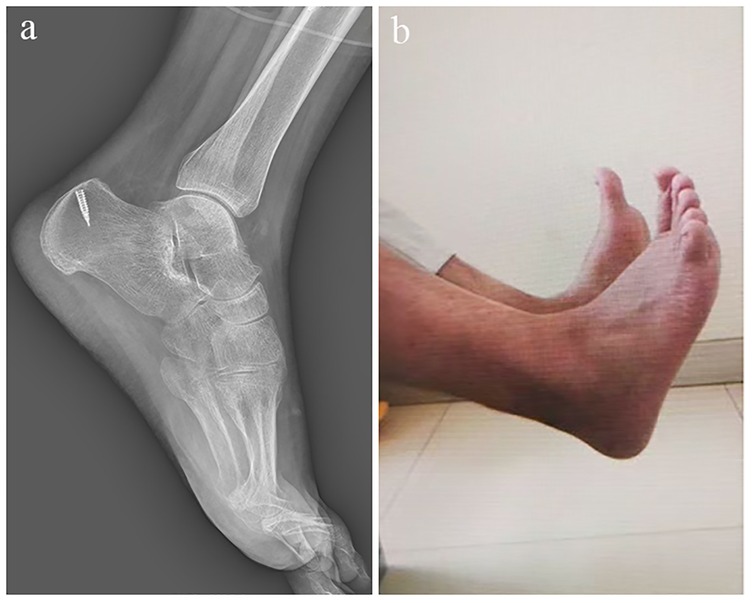

Introduction: The Achilles tendon is the largest tendon in the human body and is prone to rupture when subjected to excessive dorsiflexion trauma of the ankle joint. The primary goal of treatment is to restore limb function; however, there remains considerable debate regarding the optimal management strategy. Patient Concerns: We report a patient presenting with chronic Achilles tendon rupture accompanied by calcification of the tendon, which caused persistent pain and functional limitation of the affected limb. Diagnosis: Chronic Achilles tendon rupture with associated tendon calcification, with a tendon defect measuring approximately 6 cm on preoperative imaging, confirmed by clinical examination and imaging evaluation. Interventions: The patient underwent surgical removal of the calcified lesion, followed by reconstruction of the tendon defect using a gastrocnemius aponeurosis flap combined with the Achilles tendon sheath. Outcomes: Postoperative recovery was favorable, and at the 6-month follow-up, the patient achieved satisfactory ankle function with an AOFAS score of 89, a VISA-A score of 91, and an ATRS score of 90. At the 12-month follow-up, functional outcomes remained stable, with an AOFAS score of 95, a VISA-A score of 96, and an ATRS score of 94, confirming sustained recovery and tendon integrity. Conclusion: This case highlights a feasible surgical strategy for chronic Achilles tendon rupture with calcification, which may provide an alternative approach for tendon reconstruction in patients with sheath proliferation and calcified lesions.